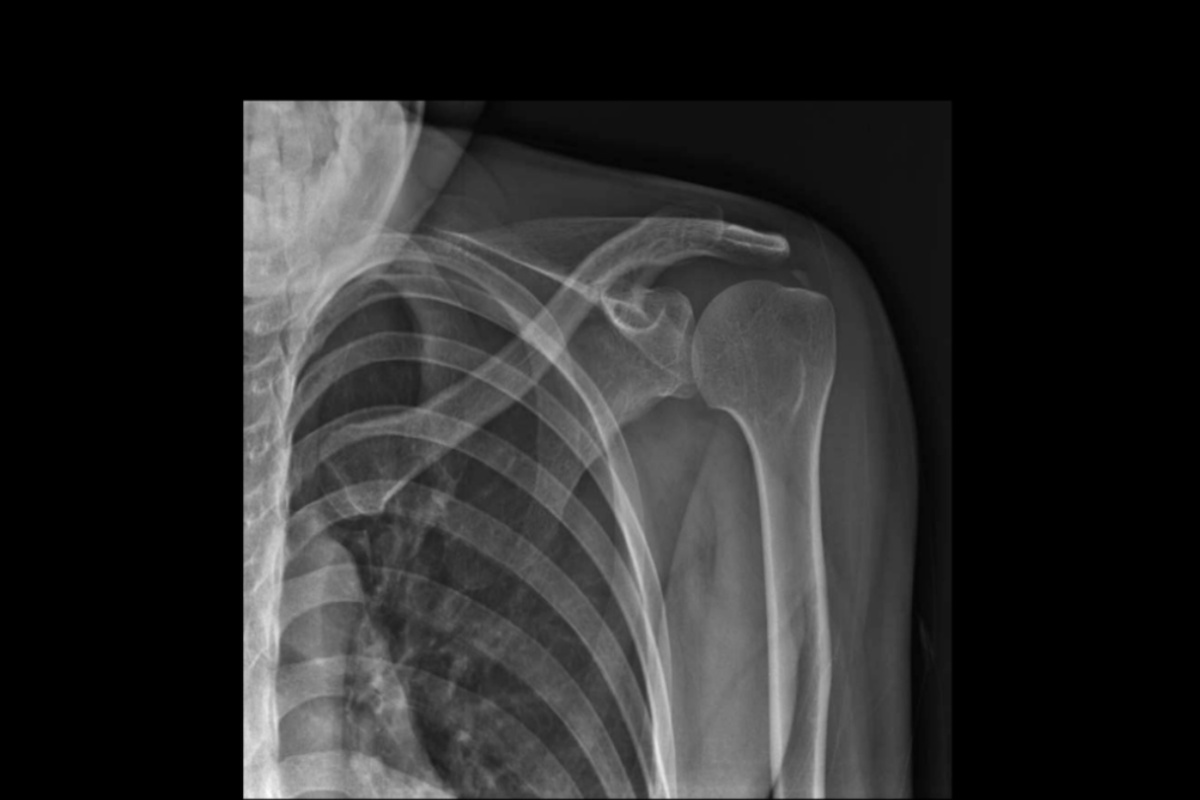

2. تصویربرداری

- MRI (تصویربرداری رزونانس مغناطیسی): بهترین روش برای دیدن پارگی تاندون و میزان آسیب عضله.

- اولتراسوند (سونوگرافی): برای ارزیابی پارگیهای ناقص و وضعیت تاندونها مفید است و قابلیت بررسی حرکتی شانه را هم دارد.

- X-ray: برای بررسی استخوان، اسپور استخوانی یا سایر تغییرات ساختاری شانه استفاده میشود، اگرچه پارگی تاندون را بهطور مستقیم نشان نمیدهد.

ترکیب معاینه بالینی و تصویربرداری باعث میشود تشخیص دقیقتر باشد و از اشتباهات رایج، مثل نسبت دادن درد شانه یا علت درد بین دو کتف به مشکلات دیگر، جلوگیری شود.